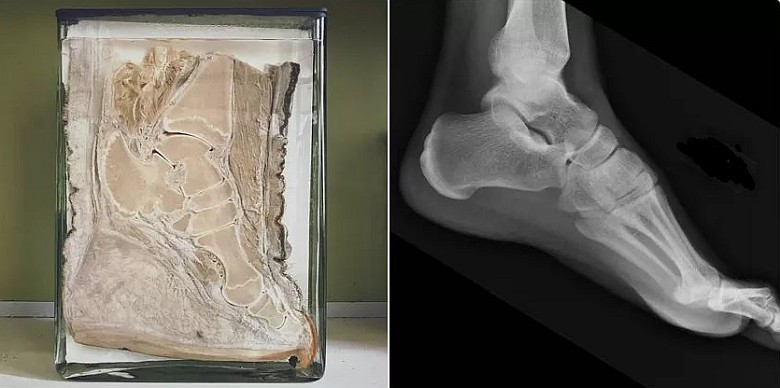

Stopa słonia i człowieka